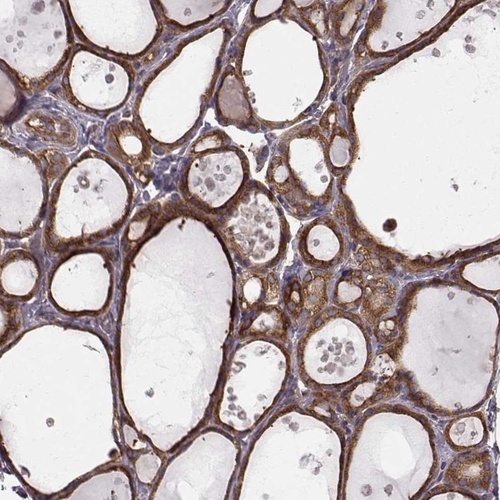

Immunohistochemistry analysis in human thyroid gland and liver tissues using Anti-RABGAP1 antibody. Corresponding RABGAP1 RNA-seq data are presented for the same tissues.